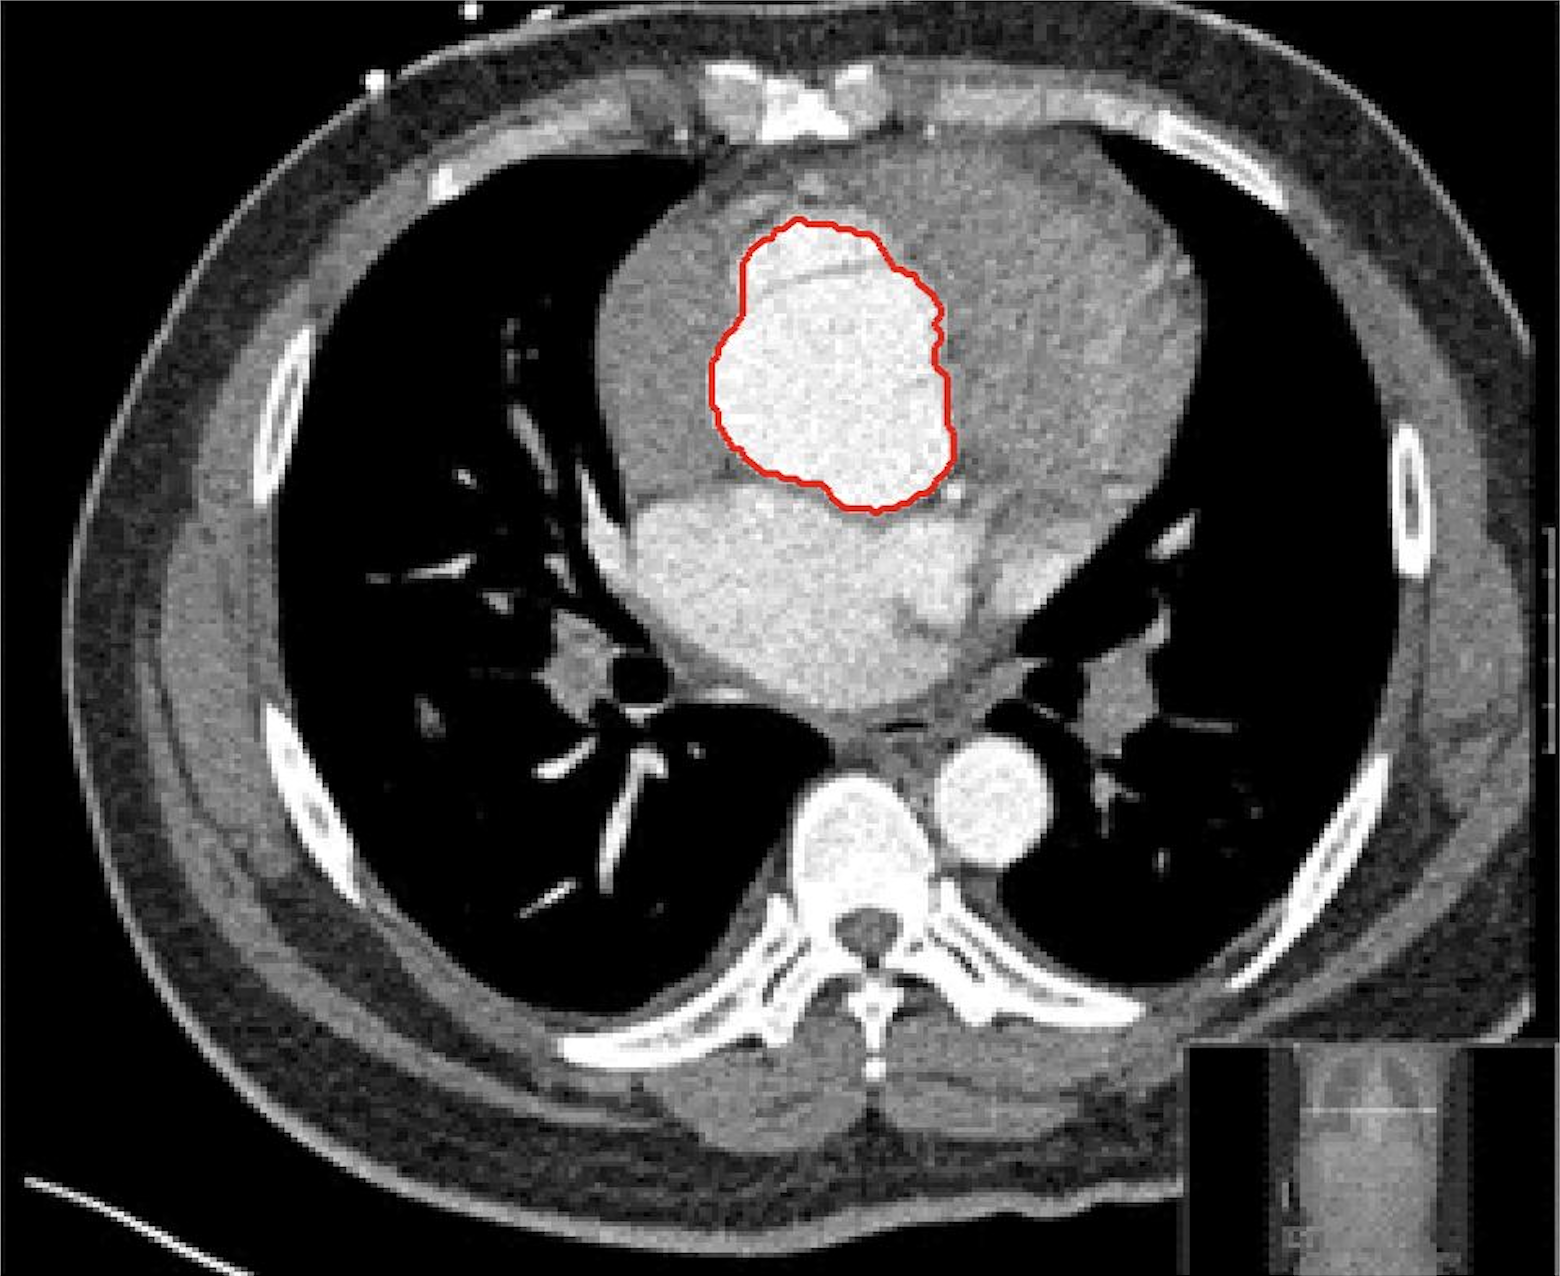

Four sets of test results are shown below. In Test 1 we compare models M1 – M6 to the proposed model M7 for two images which are hard to segment. The first is a CT scan from which we would like to segment the lower portion of the heart, the second is an MRI scan of a knee and we would like to segment the top of the Tibia. See Figure 9 for the test images and the marker sets used in the experiments. In Test 2 we will review the sensitivity of the proposed model to the main parameters. In Test 3 we will give several results achieved by the model using marker and anti-marker sets. In Test 4 we show the initialisation independence and marker independence of the Geodesic Model on real images.

Refer to captionRefer to captionRefer to captionRefer to caption

(i)                                 (ii)                                 (iii)                                 (iv)

Figure 9: Test 1 setting: (i) Image 1;  (ii) Image 1 with marker and anti-marker set shown in green and pink respectively;  (iii) Test Image 2; (iv) Image 2 with marker set shown.

Refer to caption

(a) M1 (Left to right:) Test Image 1 with markers (red) and anti-markers (blue), foreground segmentation and background segmentation (we used published software, no parameter choice required).

(b) M2 λ=1𝜆1\lambda=1, γ=10𝛾10\gamma=10.

(c) M3 λ=5𝜆5\lambda=5, θ=3𝜃3\theta=3.

(d) M4 λ=1/4𝜆14\lambda=1/4.

(e) M5 λ=5,γ=3,θ=110formulae-sequence𝜆5formulae-sequence𝛾3𝜃110\lambda=5,\gamma=3,\theta=\frac{1}{10}.

(f) M6 λ=15,θ=3formulae-sequence𝜆15𝜃3\lambda=15,\theta=3.

(g) M7 λ=10,θ=1formulae-sequence𝜆10𝜃1\lambda=10,\theta=1.

Figure 10: Visual comparison of M1 – M7 results for Test Image 1. M1 segmented part of the object, M2 – M4 failed to segment the object, M5 gave a reasonable result (though not accurate) and, M6 and M7 correctly segmented the object.